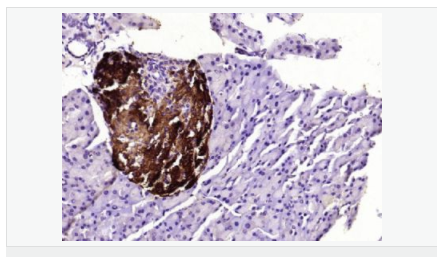

| 產(chǎn)品應(yīng)用 | WB=1:500-2000 ELISA=1:5000-10000 IHC-P=1:100-500 IHC-F=1:100-500 ICC=1:100-500 IF=1:100-500 (石蠟切片需做抗原修復(fù)) not yet tested in other applications. optimal dilutions/concentrations should be determined by the end user. |

| 細(xì)胞定位 | 細(xì)胞漿 |